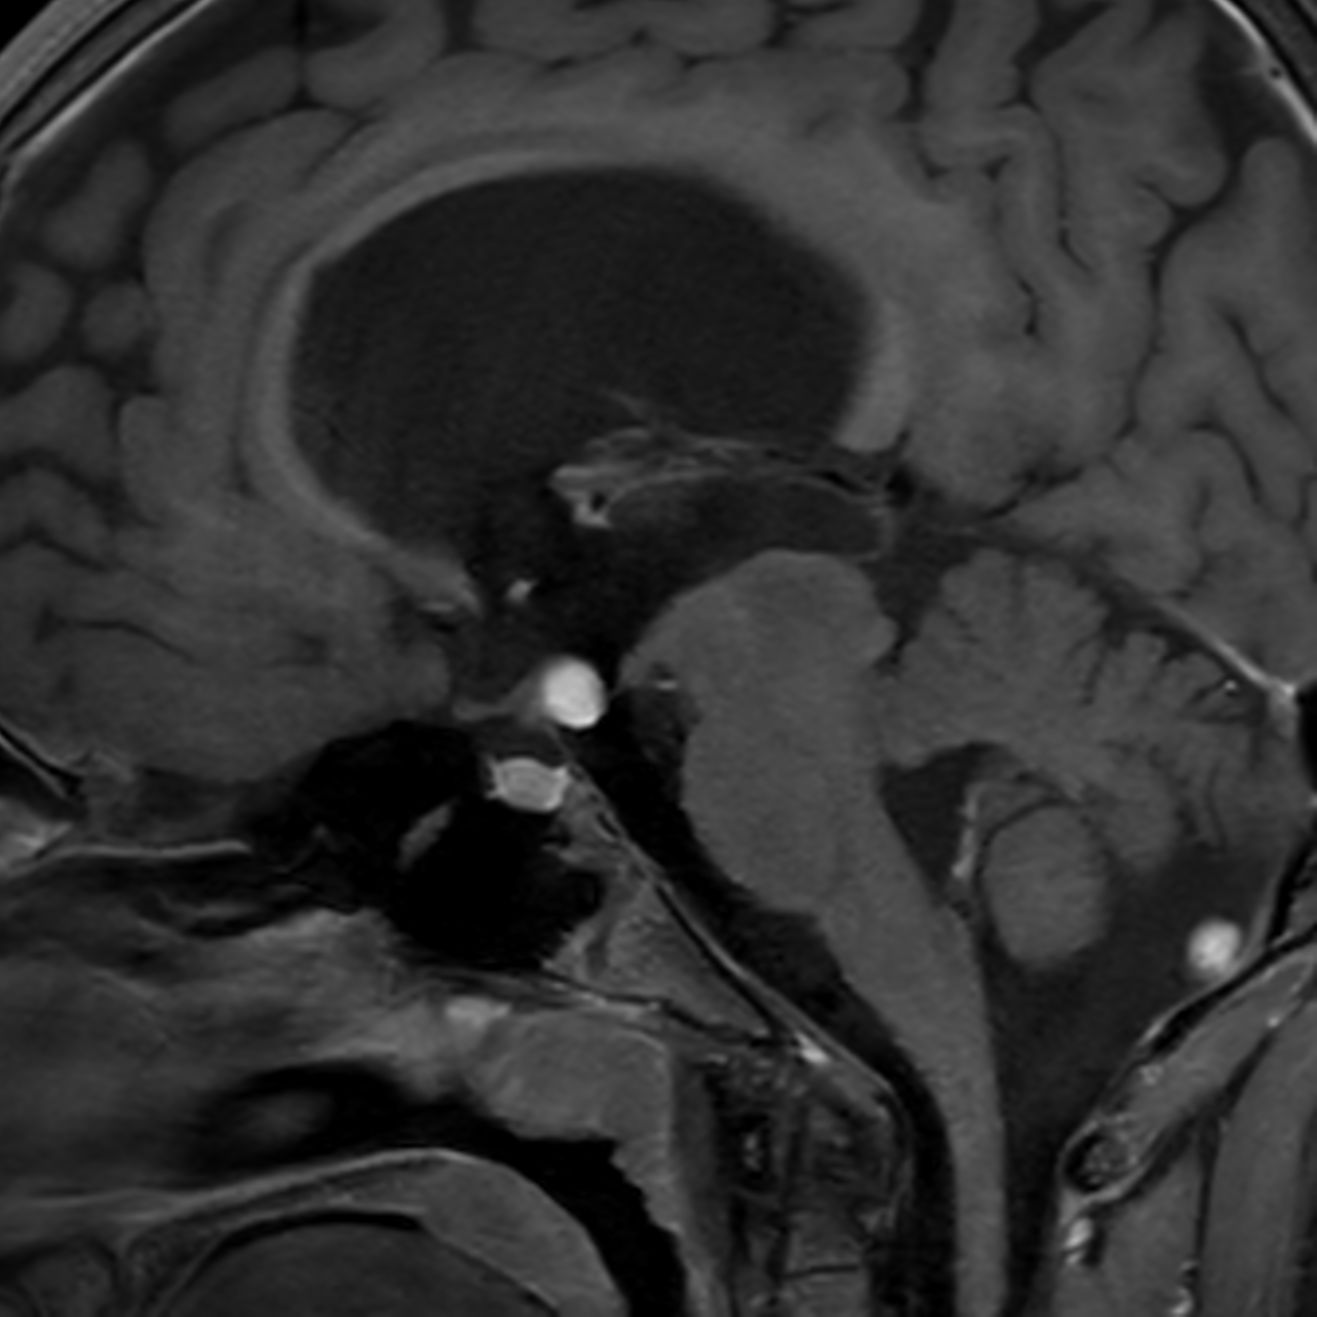

Follow up study of a 12 year old boy with a known low grade glioma.

Sagittal 3D bFFE XD